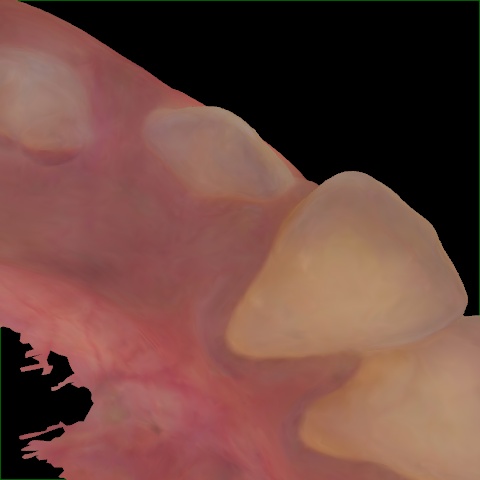

NHD25470

Annotated as "Good"

Original Image Rendering Image